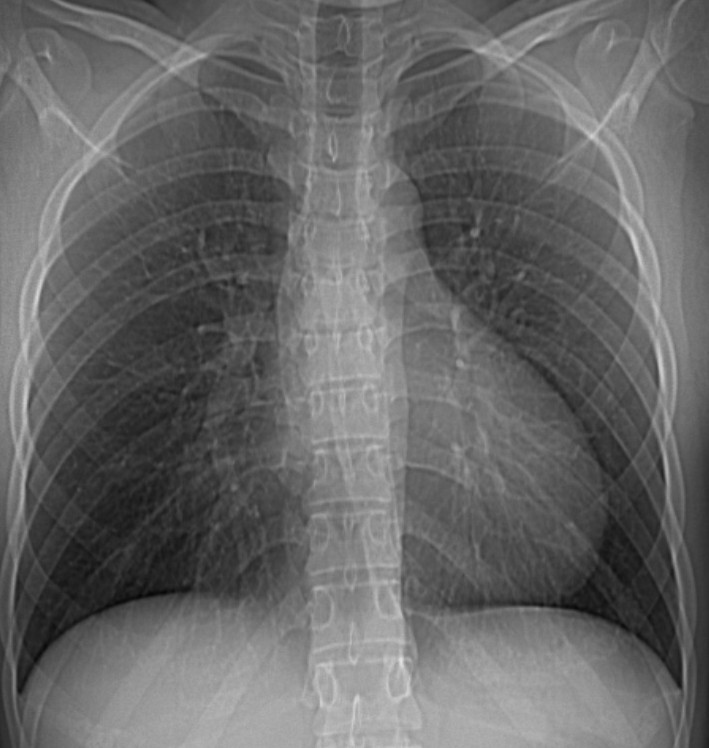

CASO: Operada de esofaguectomia y reconstrucción con coloplastia hace 3 meses. Sintomas de neumonía.

Hallazgos:

- De inicio llama la atención una densidad practicamente total del todo el hemitórax izquierdo, lo cual podría hacernos pensar que estamos ante una posible neumonía.

- Sin embargo el tórax está no está bien centrado, observar como la clavícula izquierda se encuentra casi en la mitad del pulmón, por tanto lo que vemos blanco es el mediastino ya que el tórax está rotado.

CENTRAJE:

El correcto centraje se determina comprobando que las extremidades internas de ambas clavículas equidistan de las apófisis espinosas vertebrales.

Mismo paciente, al cual esta vez se le ha tomado una radiografía en PA y en sedestación. Observar como las clavículas están equidistantes a las apófisis espinosas y como ha desaparecido el velamiento del pulmón izquierdo.

Por otra parte, paciente presenta una cardiomegalia y un discreto ensanchamiento del mediastino es probable relación con cambios postquirúrgicos.